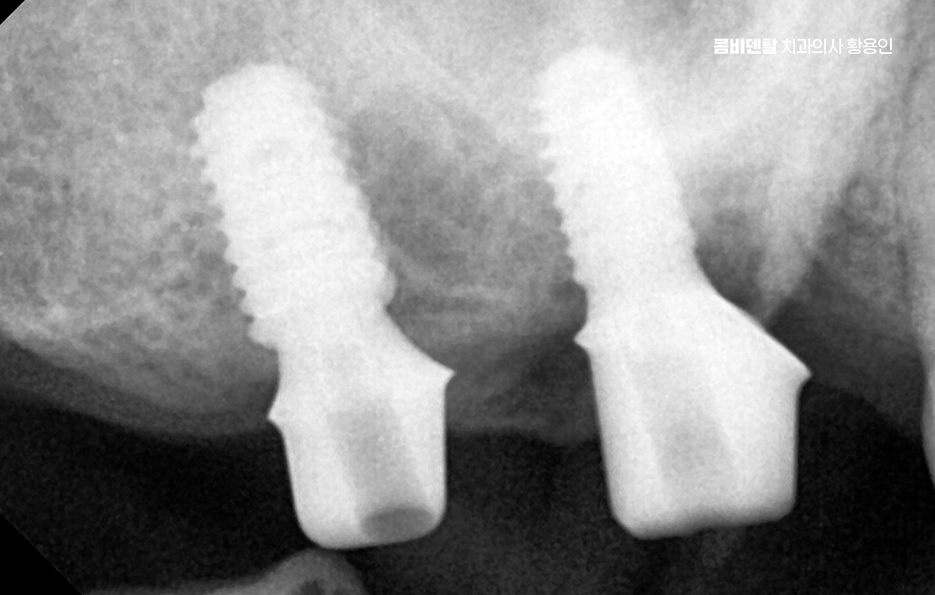

그래서 이런 문제들을 막기 위해서라도 임플란트는 어금니 상실 후 중요한 치료 옵션으로서 임플란트는 빠진 치아의 뿌리 역할까지 해주기 때문에, 단순히 공간을 채우는 게 아니라 턱뼈에 자극을 줘서 뼈 흡수를 막아주고, 위아래 치아가 정상적으로 맞물릴 수 있게 해주며 다른 보철 방식과 비교해도 장기적인 안정성과 기능 회복 면에서 유리한 거예요.

임플란트를 빨리 하는 게 좋은 이유는, 시간이 지나면서 턱뼈가 점점 흡수돼버리면 임플란트를 심을 뼈 자체가 부족해지는 상황이 생기기 때문이며 이때는 뼈이식이나 상악동 거상술 같은 추가 수술이 필요하게 되고, 치료 기간도 길어지고, 비용도 많이 올라가기 때문에 어금니가 빠졌다고 방치하는 시간만큼 치료는 더 복잡해질 수 있다는 점에서 어금니 없으면 얼굴 발음 및 오늘 알아본 것처럼 다양한 문제로 이어질 수 있음을 잘 이해하여 빠르고 나에게 맞는 치료 계획을 세우시고 장기적으로는 수명 유지까지 잘 고려하여 치료 계획을 잘 세워보시길 바라고 있어요